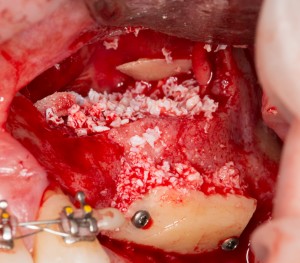

Другой метод остеопластики называется «направленной тканевой (или костной) регенерацией». Для успешной его реализации необходимы барьерные мембраны, нередко — дополнительные биоматериалы, пины и т. д., что существенно (иногда в два раза) повышает стоимость хирургического вмешательства. Но живые клетки — основа регенерации костной ткани, — в этом случае забираются в виде аутокостной стружки, а не блока, поэтому травматичность данного метода ниже, чем при аутотрансплантации. Результаты, предсказуемость, надежность — те же самые:

Еще существуют комбинированные методики остеопластики, но они применяются в ситуациях существенной утраты костной ткани, когда аутотрансплантация костных фрагментов или направленная тканевая регенерация не могут обеспечить достаточные объемы восстановления кости:

Операция заняла всего 60 минут, послеоперационные явления были настолько незначительны, что пациентка чуть ли не через пару недель решилась на вторую операцию:

Вторая операция заняла чуть больше времени (90 минут), поскольку потребовалось удаление ретинированного зуба мудрости и синуслифтинг. Послеоперационные явления более выраженные — отек держался в течение нескольких дней, болезненных ощущений почти не было.